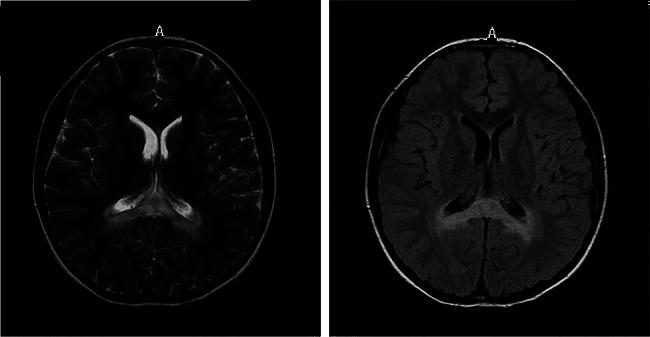

Two patients were included in this study. Both of them had significantly increased adrenocorticotropic hormone level and skin and mucosal pigmentation. They were initially clinically diagnosed with Addison's disease and received hydrocortisone treatment. However, both patients developed progressive neurological symptoms following infectious disease. Further brain magnetic resonance imaging was completed, and the results suggested demyelinating lesions. Molecular genetics suggested variations in the ABCD1 gene, which were c.109_110insGCCA (p.C39Pfs*156), c.1394-2 A > C (NM_000033), respectively. Therefore, the two patients were finally diagnosed with X-ALD, whose classification had progressed from X-ALD (Addison's-only) to childhood cerebral adrenoleukodystrophy (CCALD). Moreover, the infection exacerbates the demyelinating lesions and accelerates the onset of neurological symptoms. Neither the two variation sites in this study had been previously reported, which extends the ABCD1 variation spectrum.

本研究纳入了 2 名患者。他们均有明显的促肾上腺皮质激素水平升高和皮肤及黏膜色素沉着。最初临床诊断为 Addison 病,接受了氢化可的松治疗。然而,两名患者在感染性疾病后均出现进行性神经症状。进一步行脑磁共振成像检查,结果提示脱髓鞘病变。分子遗传学提示 ABCD1 基因存在 c.109_110insGCCA(p.C39Pfs*156)和 c.1394-2 A > C(NM_000033)的变异,分别。因此,这两名患者最终被诊断为 X-ALD,其分类由 X-ALD(仅有 Addison 病)进展为儿童脑型肾上腺脑白质营养不良(CCALD)。此外,感染加重了脱髓鞘病变,加速了神经症状的发生。本研究中这两个变异位点均未见先前报道,扩展了 ABCD1 变异谱。